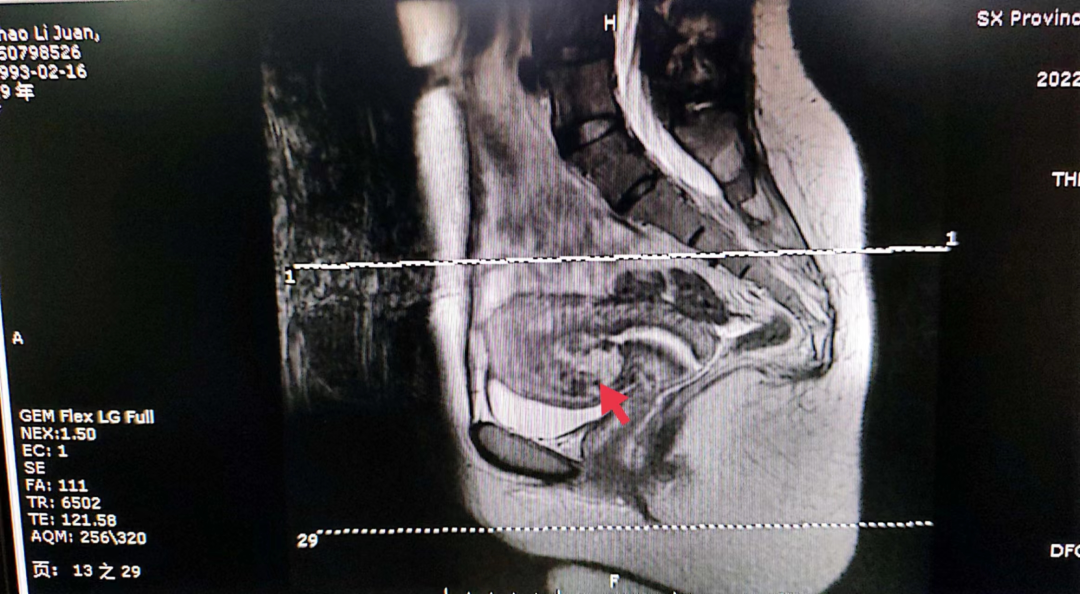

编者按 剖宫产瘢痕妊娠,是指受精卵在子宫切口上着床,在临床上这种情况要引起高度的重视,会随着妊娠囊的增大,造成局部的破裂,后果非常严重。本期【病例分析室】由山西省人民医院主任医师王素琴为大家分享一例剖宫产瘢痕部位妊娠(药流后)合并动静脉瘘,对于此情形,她是如何进行诊断和治疗的,详见以下病例分析。 病例介绍 患者29岁,主因“药流后2月,发现瘢痕妊娠4天”入院。 现病史:停经40天于当地医院行药流术,术后20天盆腔彩超未见异常。术后2月因“月经未复潮”就诊于我院,行盆腔彩超提示:瘢痕妊娠III型,动静脉瘘不除外。考虑“瘢痕妊娠”入住我科。血HCG:229.56mIu/mL。追问病史:药流术后未同房。 既往史:2009年、2021年于当地医院行剖宫产术。 婚育史:G4P2。 月经史:平素月经规律,5/25天,LMP:2022-07-01。 妇科检查:外阴正常,已婚未产型;阴道通畅,可见少许分泌物;宫颈光滑,前穹隆呈紫蓝色,触血阴性;宫体前位,大小约7*6cm大小,表面光滑,活动好,无压痛;双附件区未见明显异常。 辅助检查: 1)盆腔彩超: 子宫前壁下段瘢痕处可见44.4*34.3mm混合回声包块,向膀胱隆起,包块与膀胱间肌层变薄,厚约0.7mm,CDFI:包块内部及周边可见极丰富血流信号,可探及动静脉血流谱。考虑子宫前壁下段瘢痕处混合回声包块(瘢痕妊娠III型,动静脉瘘不除外)。 2)盆腔核磁: 子宫前壁下段瘢痕处及宫腔内见团块状异常信号影;病变周缘伴粗大迂曲血管。 3)血HCG:229.56mIu/mL。 术前诊断:剖宫产部位瘢痕妊娠III型(药流后)动静脉瘘?